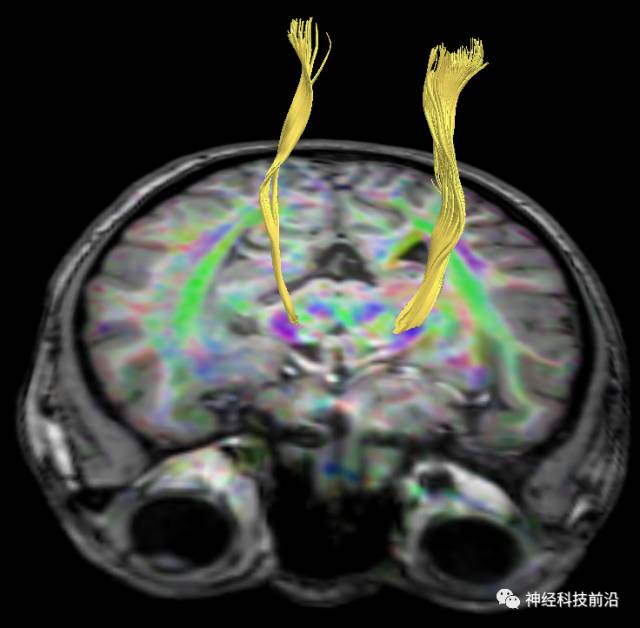

下面为皮质脊髓束的走形及位置

皮质脊髓束与皮质脑桥束的关系毗邻